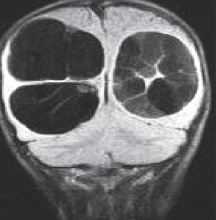

МРТ головного мозга. Корональная Т1-взвешенная МРТ. Многокамерные эхинококковые кисты.